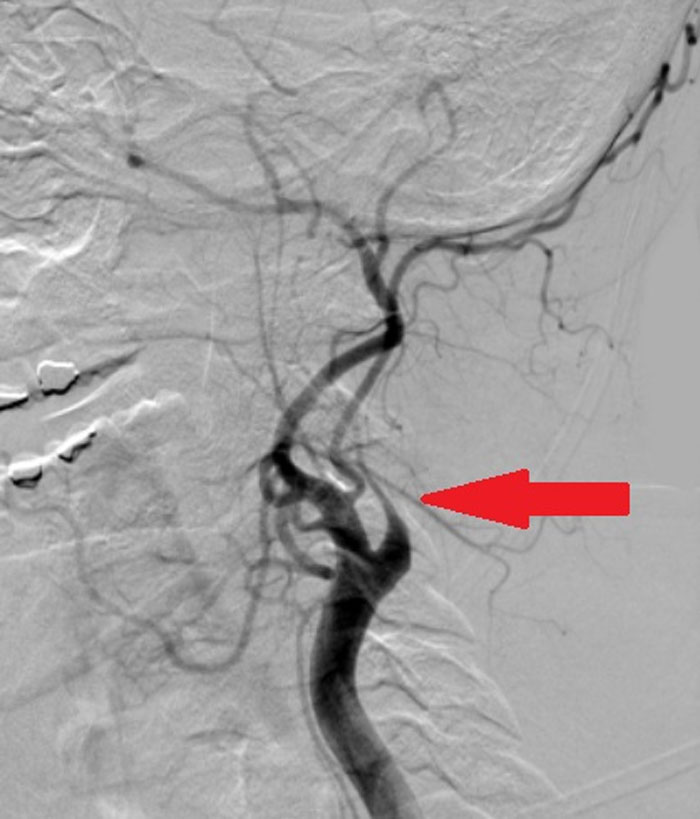

When 5-year-old Priya Galvin’s mom Mary collapsed at home from a catastrophic stroke, the girl did the only thing she could think of. She grabbed the family iPad and FaceTimed her dad, telling him that her mom wasn’t feeling well. Mary was rushed to Cork University Hospital, Ireland, where the staff there saved her life by performing a thrombectomy. Now, the entire family’s back at home and Mary is well.

According to Dr. Healy, CUH has “the busiest inpatient stroke service in Ireland.” He also mentioned that this was just one of two hospitals in the entire country that offers procedures like thrombectomies. In case you were wondering, a thrombectomy involves a specialist team removing the clot.